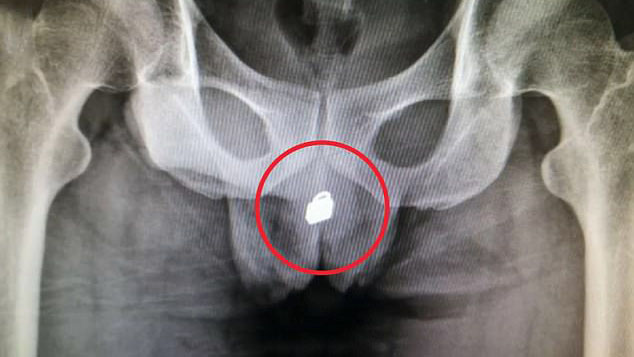

Sau khi chụp X-quang, các bác sĩ đã phân tích và xác định cần phải tiến hành phẫu thuật để tạo một lỗ hổng trên bàng quang, “mở đường” cho chiếc khóa thoát ra ngoài.

Bức ảnh cho thấy chiếc khóa bị mắc kẹt trong bàng quang của người đàn ông.

Bác sĩ phân tích sẽ tiến hành tạo lỗ hổng trên bàng quang để chiếc khóa được “giải thoát”.